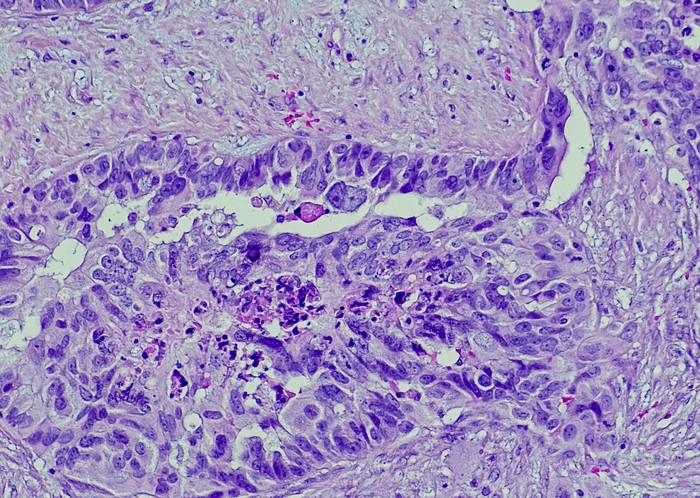

Featured photo at top of ovarian cancer cells. Photo/OGPhoto/iStock.